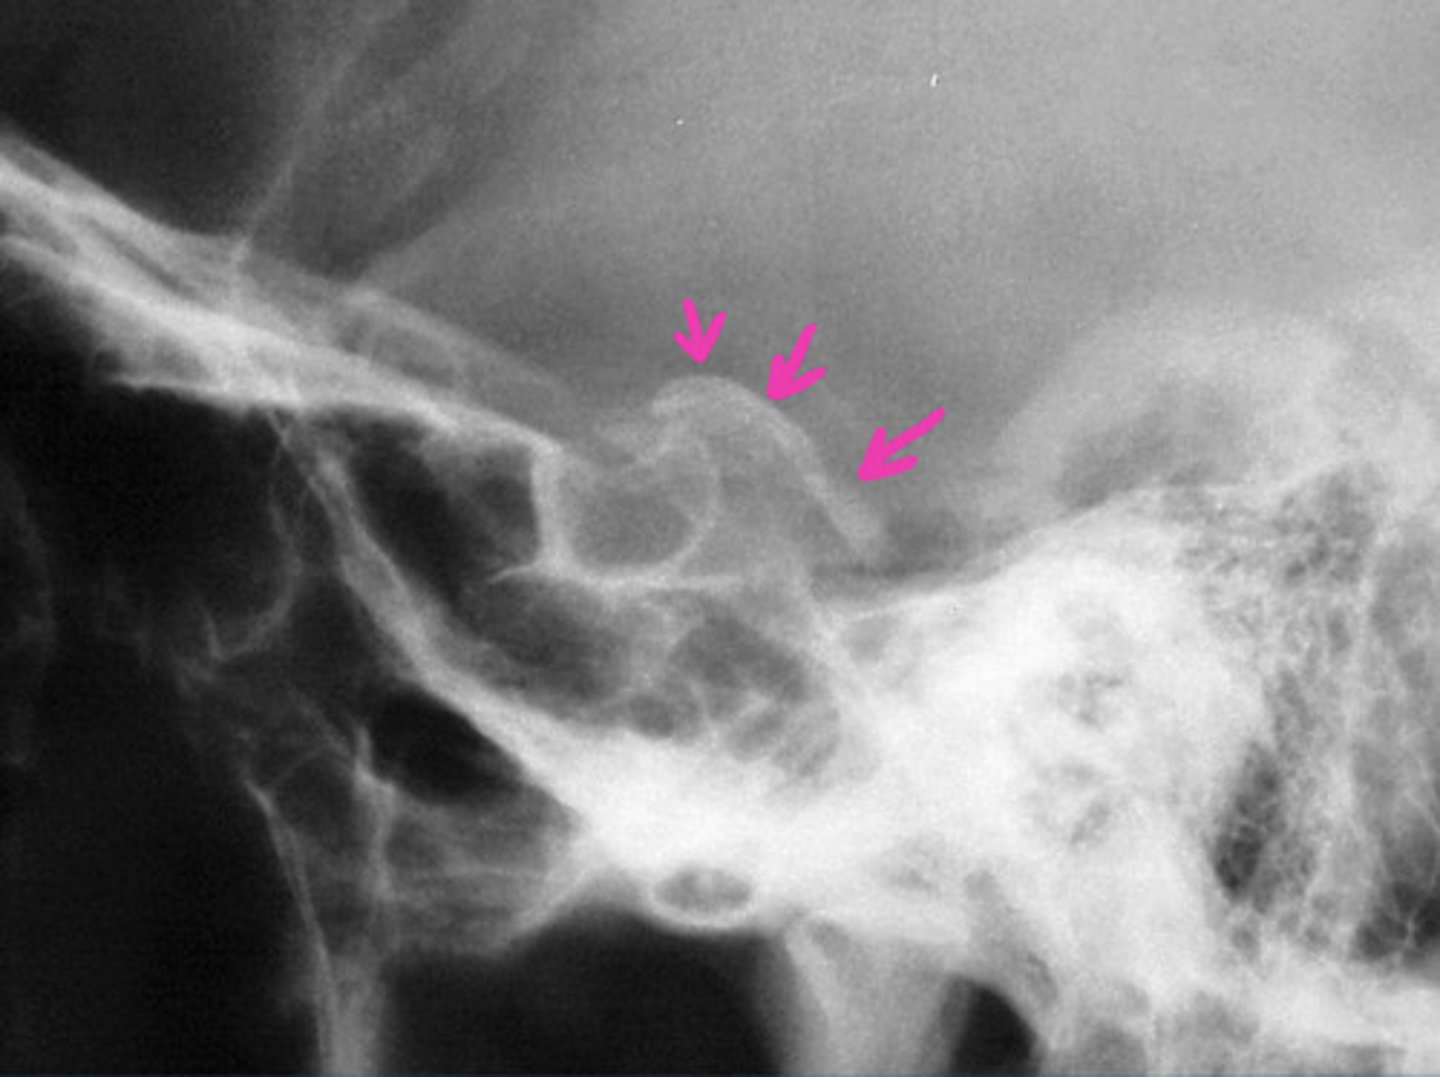

What is a common sign of NF in the spine on an X-ray?

Ribbon-shaped ribs and posterior vertebral body scalloping

Curves must be monitored carefully since they can collapse and rapidly produce paralysis